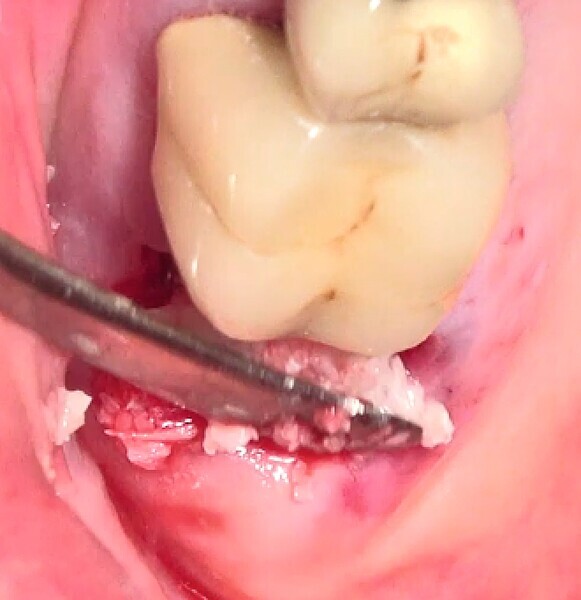

La crête alvéolaire au niveau du site de la molaire inférieure était trop étroite pour permettre la pose prédictible d’un implant sans une augmentation osseuse préalable. Des implants deux pièces en zircone ont été mis en place, simultanément à une augmentation osseuse latérale, au moyen d’une allogreffe et d’une membrane de collagène résorbable (Figs. 25–34).

Fig. 29 : Augmentation osseuse latérale (régénération osseuse guidée) au moyen d’une allogreffe constituée d’un substitut osseux, simultanément à la pose des implants.

Fig. 30 : Augmentation osseuse latérale (régénération osseuse guidée) au moyen d’une allogreffe constituée d’un substitut osseux, simultanément à la pose des implants.